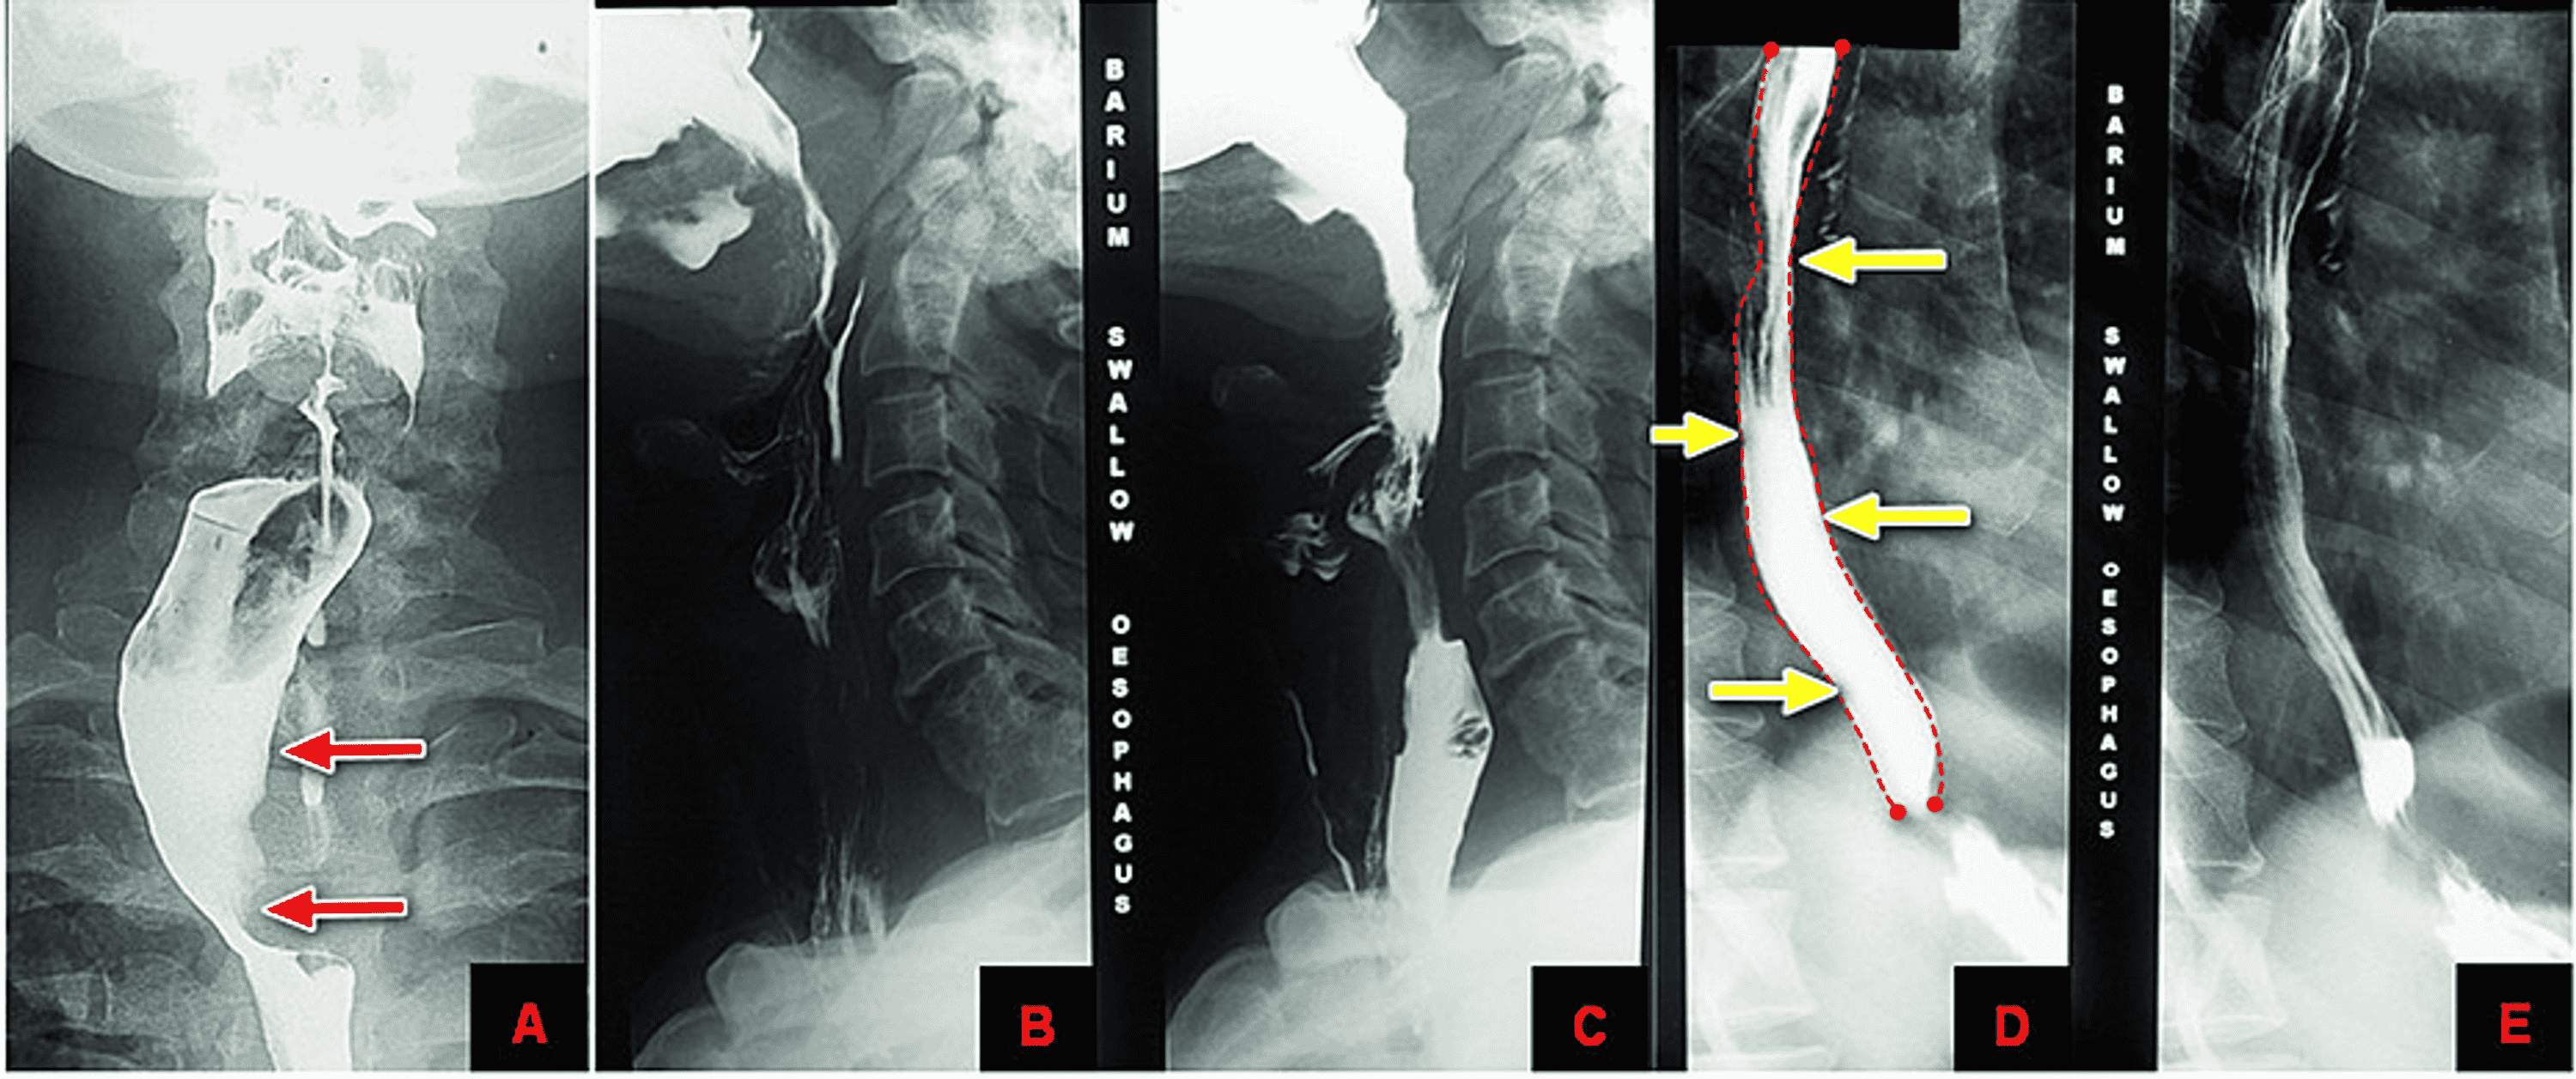

Cureus Isolated Posterior Mediastinal Thyroid Nodule Simulating

Cureus Isolated Posterior Mediastinal Thyroid Nodule Simulating What Is A Esophageal Nodule the most common type of noncancerous tumor is a leiomyoma, a tumor of the smooth muscle. updated june 1, 2022. esophagus cancers are usually found because of signs or symptoms a person is having. simple cysts are sacs filled with fluid. Many are found incidentally, remain asymptomatic, and. benign esophageal lesions have a wide spectrum. What Is A Esophageal Nodule.